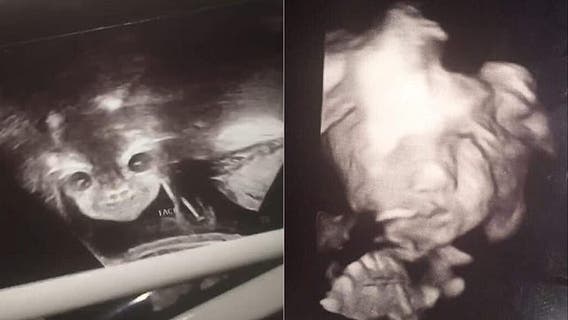

'Demon' baby shocks parents in hilarious ultrasound pics

A 17-year-old woman in Virginia went into her ultrasound appointment hoping to learn the sex of her unborn baby, but was shocked when the technician caught her daughter seemingly staring back at them like a “demon.”